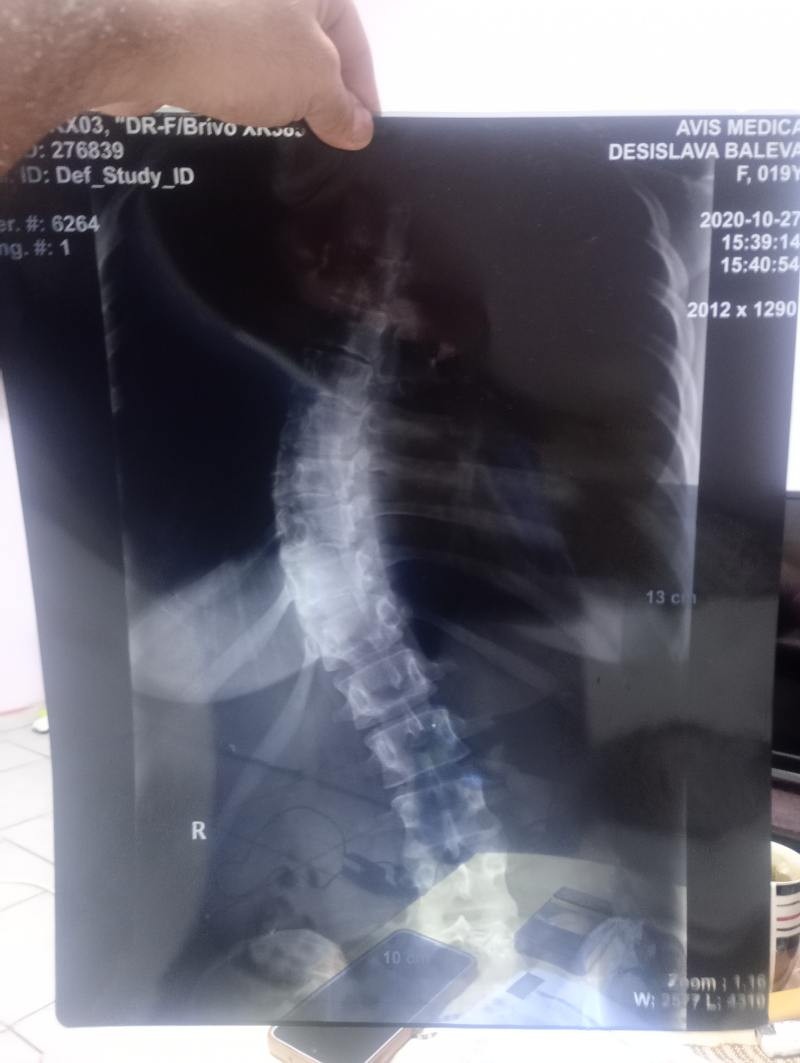

Hi, my name is Venelin, and I’m creating this fundraiser for my girlfriend, Desislava, who urgently needs surgery due to severe scoliosis.

Desislava’s scoliosis has progressed to the point where it is now affecting her heart, causing serious and dangerous health complications. Doctors have told us that surgery is urgently needed to prevent further damage and to protect her life. This has been an incredibly frightening time, and our main focus right now is making sure she gets the care she needs as soon as possible.